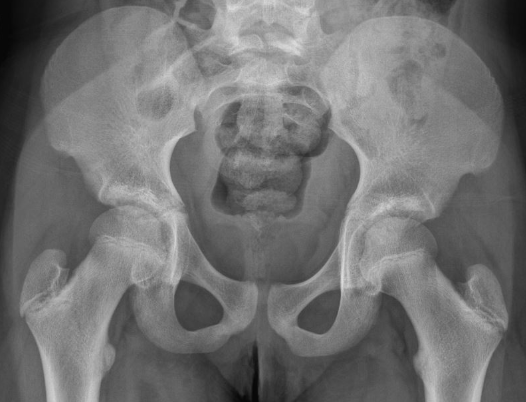

X-ray: 다른 질환(, 대퇴골두 무혈관성 괴사)과 감별